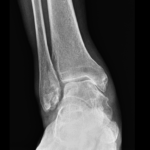

[doctormodu]1 ankle OA X-ray

04 발목 관절염 Ankle Osteoarthritis